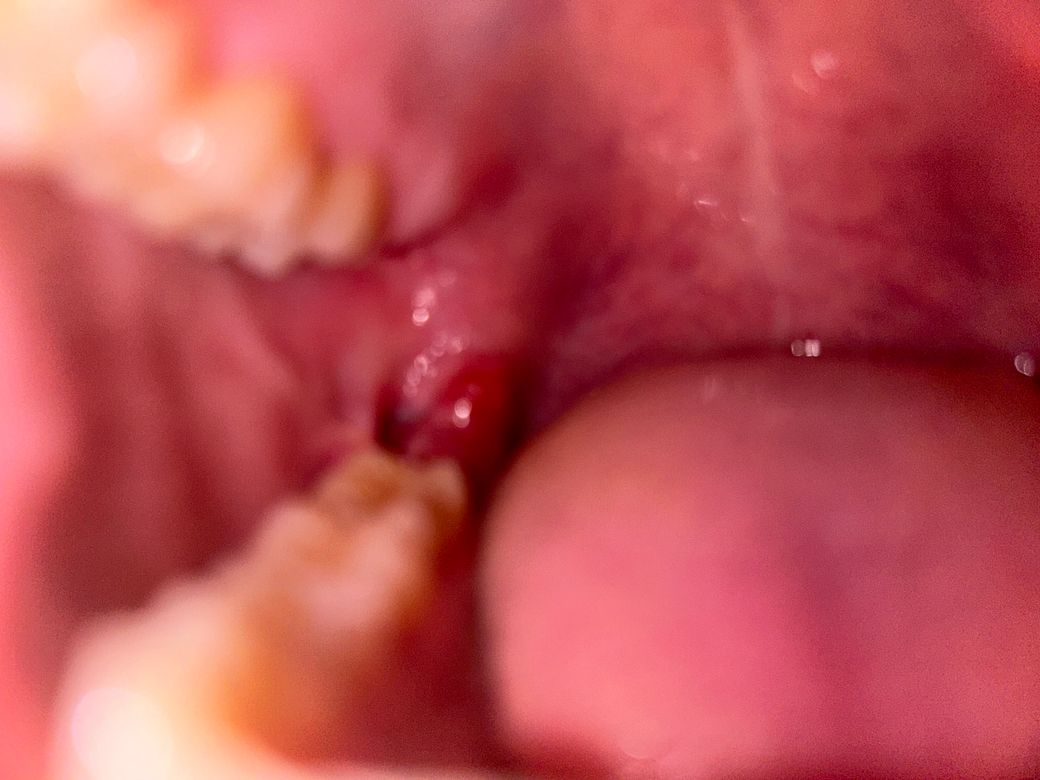

매복사랑니 발치 1주일째 상태문의(사진주의)

사진을 잘 못 찍어서 자세히 안보이지만 일단 올렸습니다.

1. 지금 볼 쪽 살(?)과 잇몸이 떨어져 있는데 괜찮은 건가요?

2. 1주일 지났는데 원래 구멍이 저렇게 큰가요?

3. 사진에 보이는 것처럼 지금 잇몸이 붉은데 괜찮은 건가요?(피가 나는 건 아닌 것 같습니다.)

• 1번 째 사진

• 2번 째 사진

• 잇몸 은 벌어져있을 수 있고 잘 낫고 있는 것으로 보입니다. 뼈가 찰 때 까지는 시린 등의 불편한 증상이 나타날 수 있습니다. 별 문제 없습니다.

• 사랑니 발치를 하고 나면 사랑니가 위치한 정도나 치아의 크기에 따라서 빈 공간의 크기의 차이가 있을 수 있습니다 이런 부위는 대부분 시간 지나면서 아무게 됩니다 잇몸이 아무런 데는 2주 정도의 시간이 걸리고 구명이 완전히 메꿔지는 데는 3개월 정도의 시간이 걸립니다

1. 네 현재 사진으로 보아서 크게 문제가 되지 않습니다.

2. 아직까지는 구멍이 있을 수 밖에 없으며 서서히 닫힙니다.

3. 아직까지 크게 문제가 없습니다.

• 1,2. 매복사랑니 발치였기에 치유에 좀 더 시간이 걸릴 수 있습니다. 보통은 1~2주차까지 잇몸 초기 치유가 이뤄집니다.

1. 정확히 보이진 않으나 잇몸 부위 혈종이 아닐까 싶습니다.